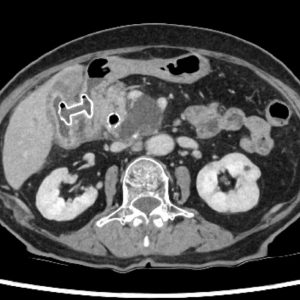

超音波・CT・MRCPなどを用いた初期診断の迅速化と、ERCP・EUS を中心とした高度内視鏡診断・治療を組み合わせ、専門性の高い一貫した医療を提供しています。

- 膵嚢胞・腹腔内膿瘍に対するEUS-TD、胆道閉塞に対する EUS-BDなどの高度治療

重症急性膵炎後のWONに対するEUS下膿瘍ドレナージ